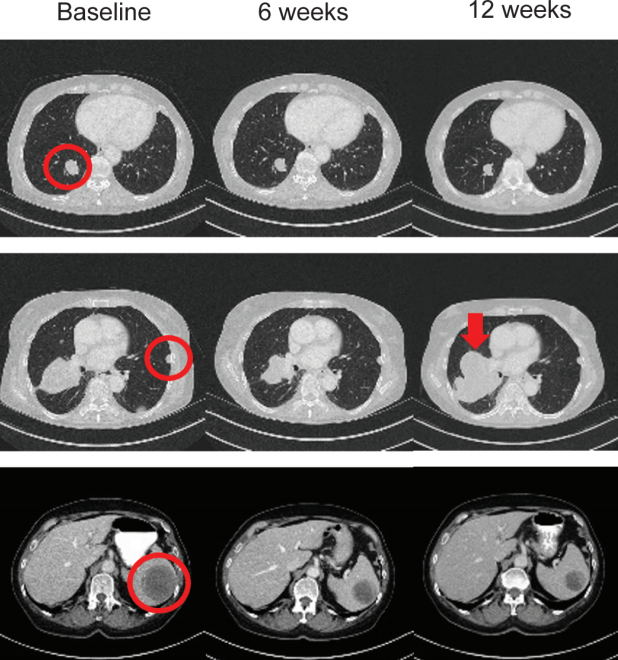

当一位26岁的年轻男性因咳嗽和胸痛被诊断为晚期肺癌时,这听起来像是一个医学悲剧。然而,当基因检测结果显示他的肿瘤携带ALK基因融合时,这个故事有了完全不同的走向。这位患者在阿来替尼治疗22个月后出现耐药,通过重复分子检测发现了ALK基因突变,换用布格替尼后12周,肿瘤缩小了90%,3个月实现了完全缓解,并持续超过12个...